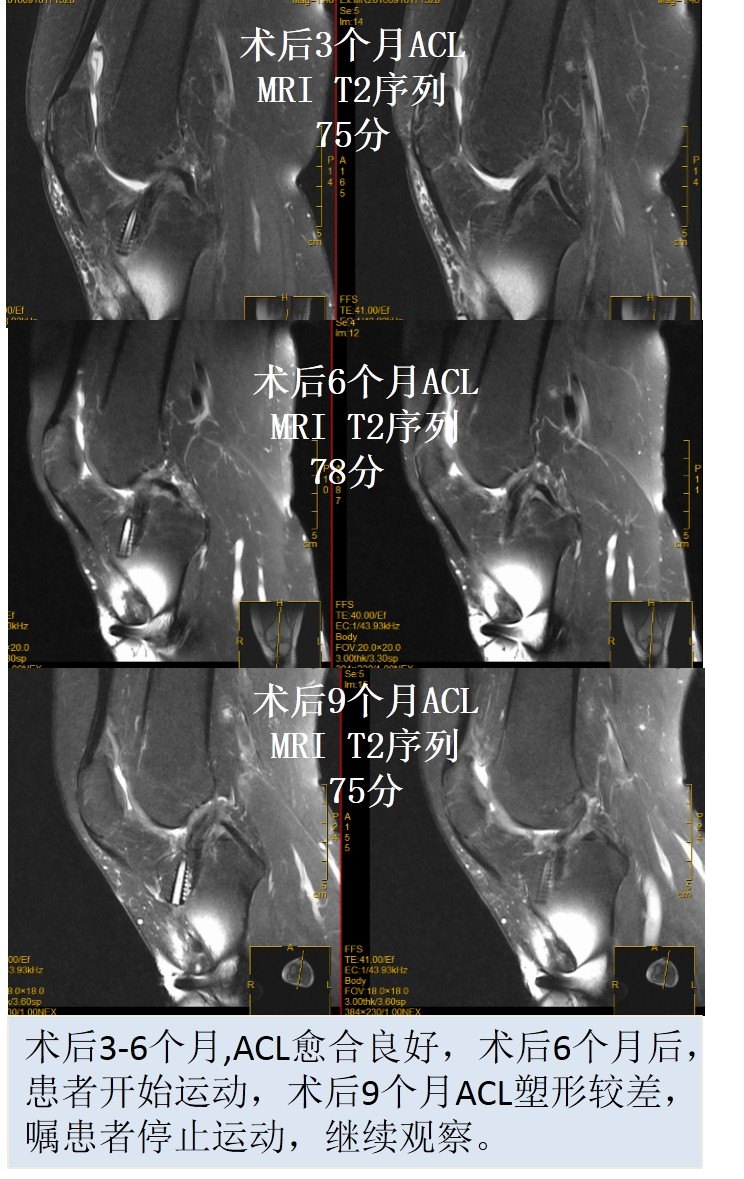

使用自体肌腱重建ACL后,移植物一般要经历缺血坏死、血管再生、细胞长入、细胞增殖和韧带塑形等四个主要过程,最终肌腱坏死后有重新成活,变成“ACL”。在人体体内肌腱塑形成ACL的过程可分为:早期阶段(0~6个月)、塑形阶段(6-12个月)和成熟阶段(12-24个月)。深刻认识这个过程有助于指导患者术后的康复,我们的观点认为,单纯ACL重建后,3个月内需要带护具慢走,6个月后可以快走,1.5年~2年后才可以恢复体育运动,在随访的每一个时间点都需要进行体格检查和核磁共振(MRI)进行评估膝关节的稳定性和韧带塑形情况。

ACL重建后进行MRI评估是评估重建ACL塑形的最直观的非创伤性检查方法。我们的观点认为,如果重建的ACL在MRI上的评分在80分以上(MRI的三个评估指标,总分90分:韧带的容积-30分;韧带的张力-30分;韧带的灰度-30分),术后膝关节功能就恢复好,再次恢复到伤前运动状态的几率就大,重建韧带发生再断裂的风险就低。而且我们在随访过程能根据重建的ACL在MRI上的评分结果调整康复进程,指导患者的运动方法,以利于重建韧带的最终塑形,这个十分重要的。

因此,进行前交叉韧带重建后,重建的韧带一直处于动态变化过程中,MRI检查能够准确的评估韧带的愈合和塑形情况!也是临床医生判断前交叉韧带重建术后韧带塑形的重要参考标志。一般认为,前交叉韧带术后3个月、6个月、12个月、18个月和24个月是进行MRI检查的时间点,通过MRI检查,及时发现韧带塑形过程的问题,有利于指导患者的康复进程和运动方式的选择!